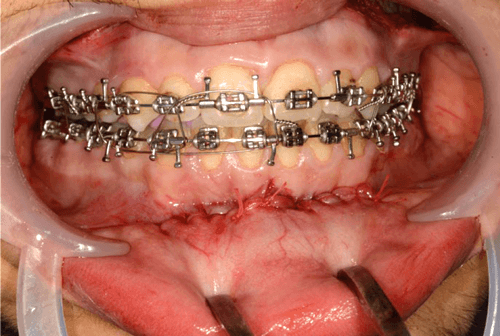

Both the mentalis muscle is re-suspended and mucosal incision is closed with 4/0 Vicryl Rapide (two layered closure) (Figure 5).

Figure 5.

We support the overlying soft tissues with a pressure chinstrap dressing which remains on for at least 24 hours. We instruct our patients to maintain an optimal level of oral hygiene and to complete a five-day oral course of antibiotics.